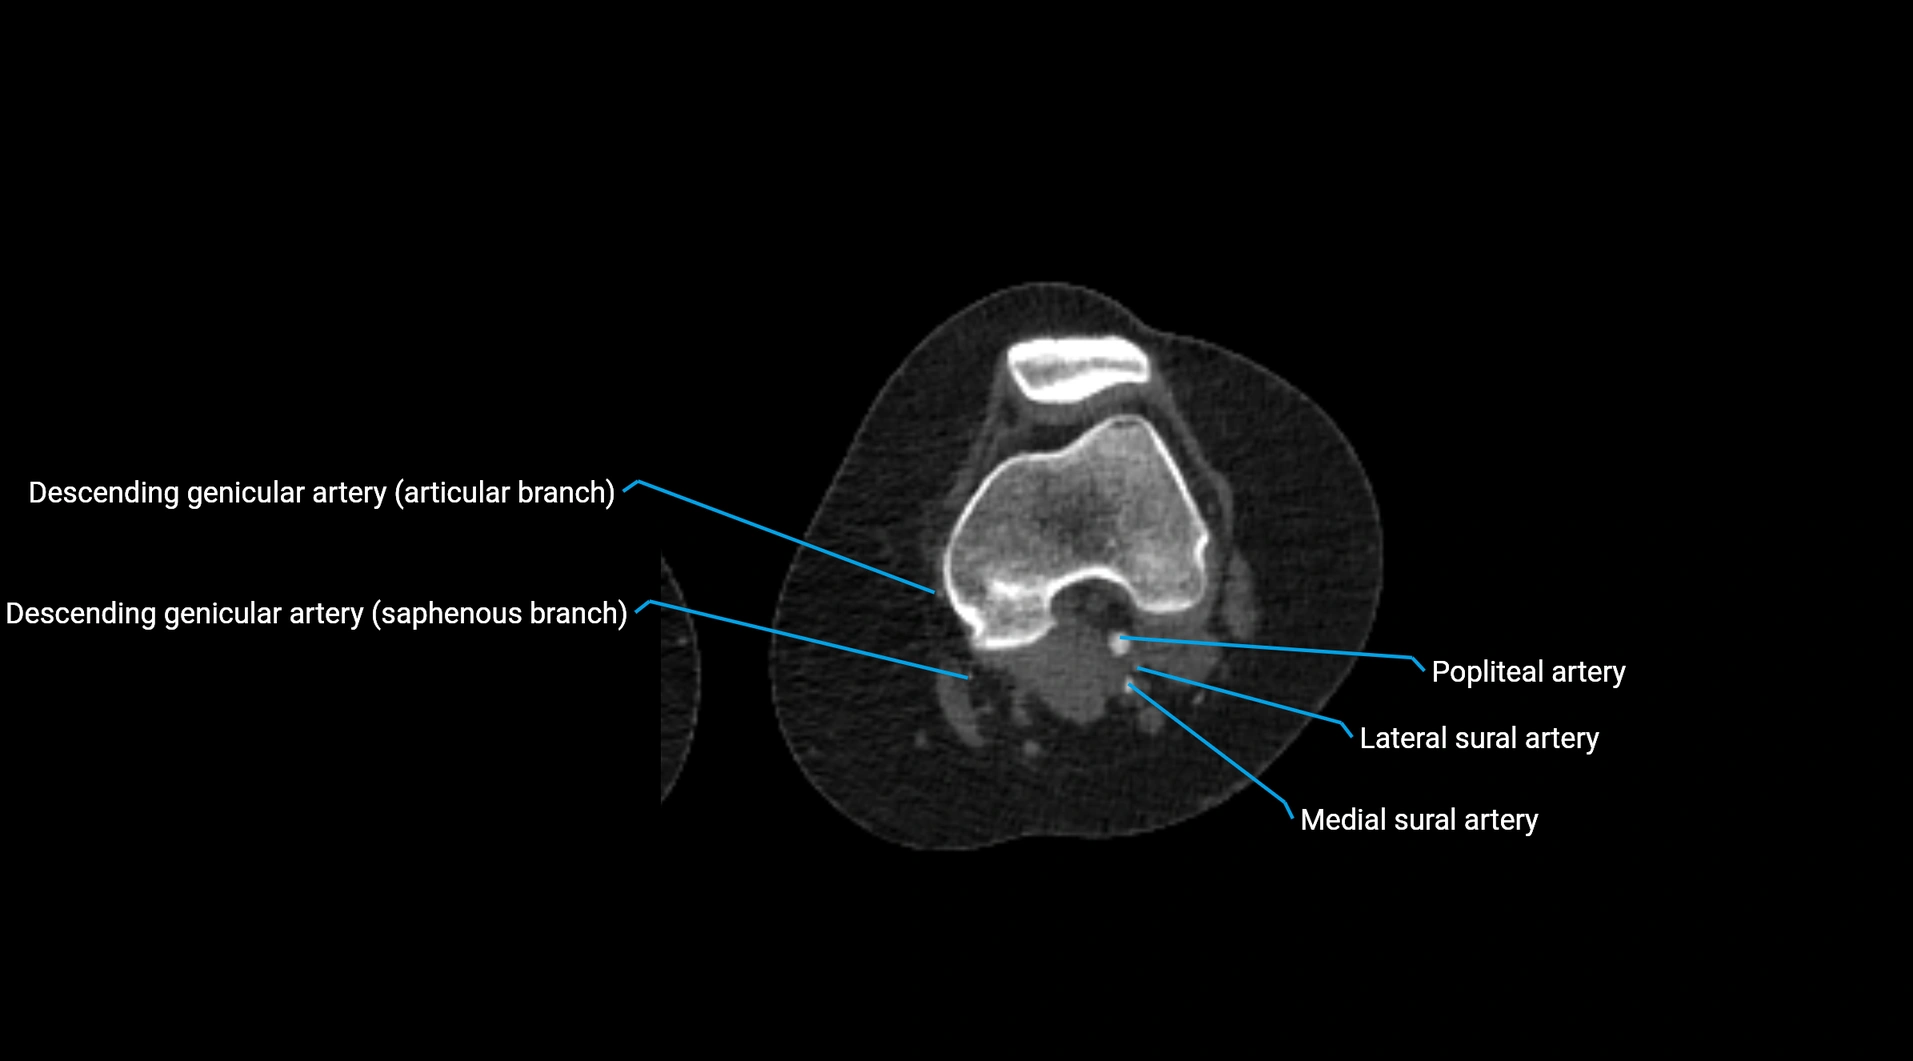

CT Appearance

Non-contrast CT:

• Appears as a tubular soft tissue structure anterior to vertebral bodies

• Calcified atherosclerotic plaques appear as hyperdense foci along the wall

• Useful for screening abdominal aortic aneurysm (AAA) size and mural calcification

Contrast-enhanced CT (CTA):

• Gold standard for abdominal aortic imaging

• Provides excellent detail of lumen, wall, aneurysm, thrombus, and branch vessels

• Multiplanar and 3D reconstructions help in aneurysm measurement, stent graft planning, and dissection evaluation

• Detects acute rupture, traumatic injury, or occlusion with high sensitivity